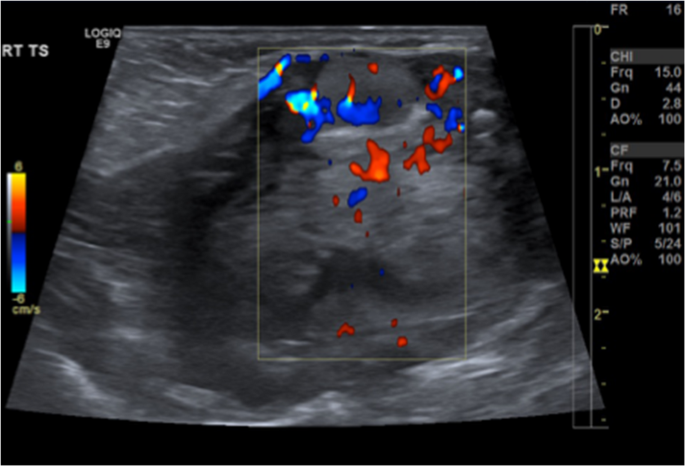

图2

颈部超声检查(含多普勒显示)显示颈部甲状软骨上方有一个6.5毫米×5.6毫米的甲状腺组织结节,多普勒显示该结节有血管供应

母亲的甲状腺过氧化物酶(TPO)抗体和TFTs检测结果正常。静脉注射99m锝后进行甲状腺闪烁扫描,标准前后位图像显示舌下区域有放射性摄取,而颈部没有放射性摄取。甲状腺超声检查证实舌下有一个不到一厘米的异位甲状腺组织结节,诊断为舌下甲状腺伴半发育不全(见图12)。